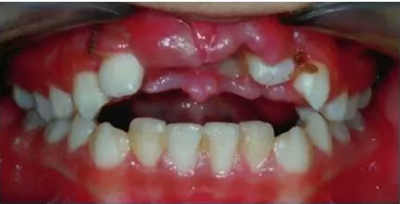

車禍后,一名10歲男孩被送往Shariati醫(yī)院急診科。診斷出上頜中切牙的脫落和側(cè)切牙的嵌入(圖1)。脫落的中切牙丟失了,沒有進(jìn)行再植。全景片示除第二磨牙外的恒牙列(圖2)。

圖1. 初診口內(nèi)照